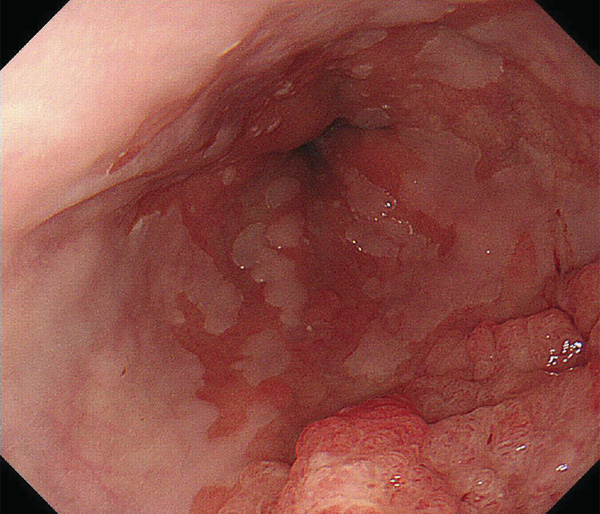

内視鏡所見と病理組織像の1対1対応が可能な症例を公募いたします。主にLSBEに発生した早期癌(HGDを含む)を対象としますが、興味深い症例であればSSBE癌でも結構です。採否は世話人へご一任ください。

症例呈示希望者は応募用紙に記入の上、代表的な内視鏡(2枚)、切除標本(新鮮、固定)、切り出し図、マッピング、代表的組織像とともに、Barrett 食道研究会事務局 barrett.shinshu@gmail.comへお申し込み下さい(10MB以下でお願い致します)。

特に、本邦では極めて稀なlong segment Barrett’s esophagus(LSBE)から発生した早期癌は、診断に難渋する場合も多く、欧米ではランダム生検による検出が標準的とされています。背景のBarrett食道もろとも全体を内視鏡切除+ラジオ波焼灼する欧米と異なり、ESDで内視鏡的な局所切除が基本の本邦では、存在診断+範囲診断(特に水平)を的確に行うことが不可欠です。

そのためには、一流の病理医による組織学的診断とエキスパート内視鏡医による拡大内視鏡像との一対一対応を徹底的に行うことで、『本来、見えないであろう拡大所見の先にある組織構築像が診えてくる』所まで内視鏡診断レベルを上げていく必要があります。その実現には、一対一対応を追究した症例(特にLSBE発生例)1例でも多く経験するしかありません。本研究会でBarrett食道腺癌(LSBE発生早期病変)を共に学び、拡大内視鏡像の一歩先を診るスキルを習得しましょう!一人でも多くの皆様のご参加をお待ちしています。